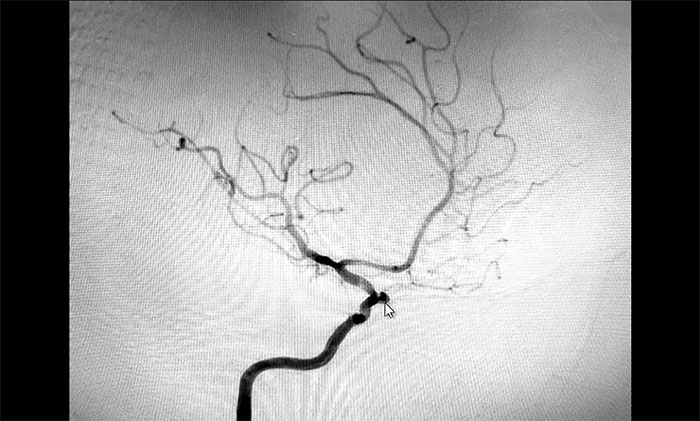

考虑脑出血后遗症可能,于耀宇主任为秦女士完善相关检查。通过DSA全脑血管造影检查,发现患者右侧颈内动脉眼动脉段动脉瘤形成,瘤囊直径约3mm,就像一颗长在动脉血管上的“葡萄”,里面充盈流淌着血液。

▲ DSA检查发现颅内动脉瘤